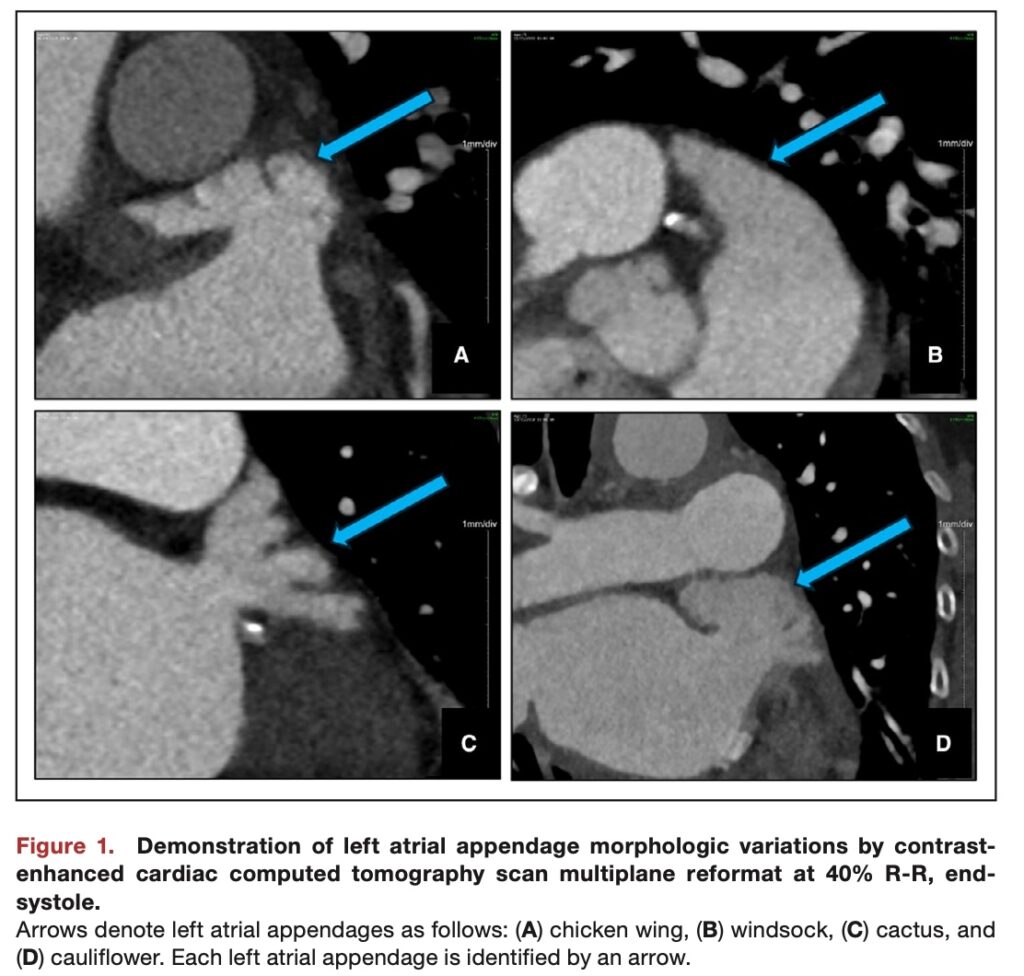

形態の分類は、既存の解剖学的基準に従い

・chicken wing チキンウィング

・windsock ウィンドソック

・cactus カクタス

・cauliflower カリフラワー

の4型に分けられ、それぞれに血栓形成の相対リスクに応じた1点から8点までのスコアが割り当てられています。

補足:左心耳の4つの形態分類

左心耳の形は、主に「主幹部の長さ」「曲がり具合(屈曲)」「分葉(Lobe:枝分かれした小さな部屋)の数と複雑さ」によって分類されます。

Chicken Wing(チキンウィング型)

- 直訳: 鶏の手羽先

- 見た目: その名の通り、食べる「手羽先」のように、途中でくいっと曲がっている(屈曲がある)のが特徴です。通常、大きな一つの部屋(主幹部)で構成され、細かい枝分かれは少ないです。

- 特徴とリスク(低リスク):

- 最も一般的な形です。

- 曲がってはいますが、構造が単純で中が広いため、血液がよどみにくく、スムーズに流れます。

- そのため、4つの中で最も血栓ができにくく、脳卒中リスクが低い形とされています。

Windsock(ウィンドソック型)

- 直訳: 吹き流し(空港、ヘリポート、高速道路などで風の方向と強さを視覚的に示す、筒状、円錐形の布製チューブ)

- 見た目: 風になびく吹き流しのように、細長く伸びた筒状の形をしています。

- 特徴とリスク(中リスク):

- チキンウィングのような強い曲がりはなく、まっすぐ、あるいは緩やかに伸びています。

- 構造は比較的単純ですが、奥行きが深いため、先端部分で血液の流れが少し遅くなる可能性があります。チキンウィングよりはリスクが高いですが、後述する2つよりはマシな「中間リスク」に分類されます。

Cactus(カクタス型)

- 直訳: サボテン

- 見た目: 西部劇に出てくるような、柱サボテン(弁慶柱)を想像してください。中央の太い幹から、いくつかの「腕」が枝分かれしているような形です。

- 特徴とリスク(中~高リスク):

- 主幹部から、複数の分葉(小さな部屋)がポコポコと枝分かれしています。

- この「枝分かれした根元の部分」や「小さな部屋の中」で血液がよどみやすくなります。ウィンドソックよりも構造が複雑なため、リスクはやや高めの中間リスクと考えられています。

Cauliflower(カリフラワー型)

- 直訳: 野菜のカリフラワー

- 見た目: まさに野菜のカリフラワー(あるいはブロッコリー)の房のように、短い軸から多数の小さな房(分葉)がブワッと密集して多方向に広がっている形です。

- 特徴とリスク(高リスク):

- 最も構造が複雑な形です。

- 主幹部は短く、内部は小さな部屋が無数に入り組んでいます。野菜のカリフラワーを洗うときに房の隙間の汚れが落ちにくいのと同じで、この複雑な隙間に血液が入り込むと、流れが完全に停滞してしまいます(うっ滞)。

- そのため、4つの中で最も血栓ができやすく、脳卒中リスクが非常に高い形とされています。

心房細動における脳卒中リスクの評価において、左心耳は血栓形成の主戦場として知られています。特に左心耳の複雑な形態は、内部の血流停滞を引き起こし、血栓形成を促進します。過去の研究では、左心耳の形状を4つの典型的なカテゴリーに分類し、脳卒中リスクとの関連を論じてきました。最も低リスクとされるのが「チキンウィング(手羽先)型」であり、一方で最も高リスクとされるのが多房性で複雑な構造を持つ「カリフラワー型」です。